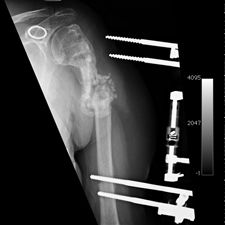

She was advised of the need to do some sort of stabilization which is necessary since the use of low-dose ultrasound has not helped in the healing process. She was unwilling to have any further operative intervention and sought further options. Eventually, she agreed to a fourth procedure of intra-medullary nail stabilization of the fracture and had this carried out in April 2011. An intramedullary nail was inserted in an antegrade manner and she has since gone on to heal the fracture site completely and has regained most of the function of the upper limb with no pain.

This case illustrates the possible complications that can occur with any surgery but also our commitment to our patients by sticking with them and making sure that a positive outcome is had despite the many challenges that may arise.